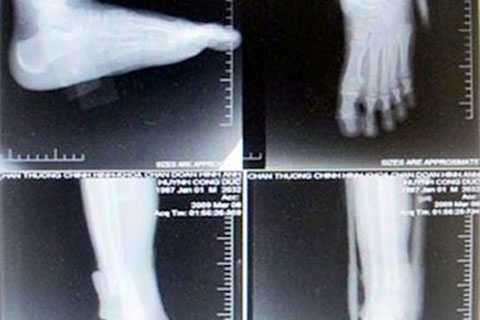

Một bệnh nhân chụp cổ bàn chân ở 4 tư thế đã bị cắt ghép phim.

Bệnh nhân phải nộp 240.000 đồng để mua hai phim chụp X-quang. Tuy nhiên, sau khi xem hồ sơ, vị BS phát hiện phiếu thu tiền chụp phim X-quang cho người bệnh là loại lớn, trong khi hai tấm phim chụp thực tế thì nhỏ, nhìn không rõ. Thay vì phải chụp trên hai phim thì kỹ thuật viên đã ghép cả bốn tư thế chụp trên một phim rồi cắt làm hai, khiến tấm phim bị teo tóp phân nửa (kích thước chỉ còn 35cm x 21,5cm). Từ sự việc trên, nhiều BS của BV tìm hiểu và phát hiện hàng trăm vụ “ăn phim” đã diễn ra tại BV này kéo dài trong nhiều năm.

Việc gian lận được thực hiện bằng hai cách: Đánh tráo phim X-quang (thu tiền của bệnh nhân với giá phim loại A, nhưng lại chụp bằng phim loại B rẻ hơn) và lắp ghép phim (người bệnh đóng tiền chụp cho 2 phim, nhưng khoa chụp ghép nhiều bộ phận cơ thể cần chụp trên 1 phim, rồi cắt nhỏ phim ra đưa cho bệnh nhân)”.

Chẳng hạn, bệnh nhân được chỉ định chụp cột sống cổ bốn tư thế: Thẳng, nghiêng, chếch 3/4 hai bên và BV sẽ thu tiền bệnh nhân là chụp 2 phim. Tuy nhiên, khi chụp, kỹ thuật viên thực hiện việc ghép chụp 2 hoặc 4 phần cơ thể trên một phim. Bệnh nhân hoàn toàn không biết kích thước chuẩn của phim là bao nhiêu, chỉ thấy kết quả chụp X-quang cho ra hình ảnh chụp của bốn tư thế trên cùng một phim của bệnh nhân và giao cho họ nhận 2 tờ phim đã cắt. Bệnh nhân nghĩ là đúng theo phiếu thu tiền 2 phim của BV.